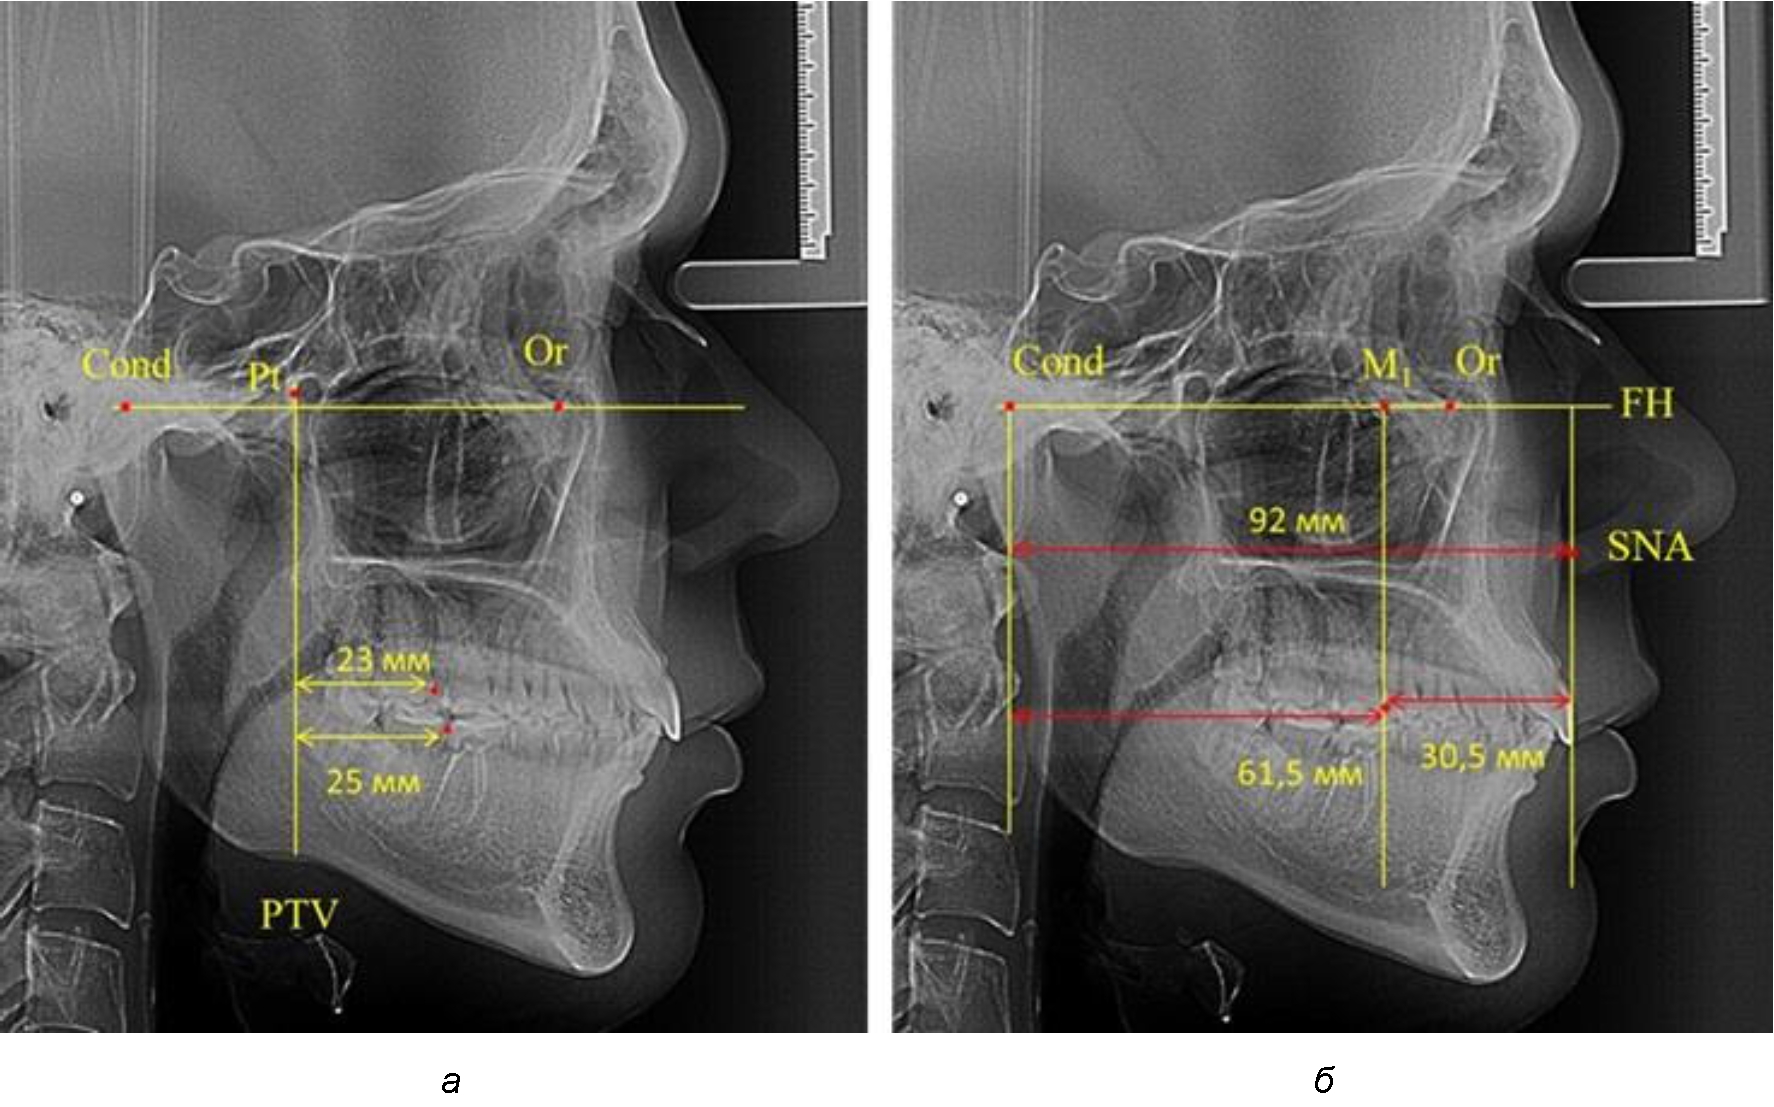

Так, при расстоянии от крыловидной вертикальной плоскости PTV до дистальной поверхности верхнего первого постоянного моляра в 13 мм сагиттальный размер гнатического отдела был 82 мм. При этом отношение кондилярно-спинального расстояния к кондилярно-молярному размеру (54,5) было близким к коэффициенту 1,5, что представлено на рис. 2.

В то же время при увеличенном расстоянии от крыловидной вертикальной плоскости PTV до дистальной поверхности верхнего первого постоянного моляра, равное 23 мм, сагиттальный размер гнатического отдела составил 92 мм. При этом отношение кондилярно-спинального расстояния к кондилярно-молярному размеру (30,5), так же, как и при малых размерах, было близким к коэффициенту 1,5, что представлено на рис. 3.

Рис. 2. Особенности положения первых моляров по R. E. McDonald (а) и по предложенному методу (б) при уменьшенном молярно-крыловидном расстоянии

Рис. 3. Особенности положения первых моляров по R. E. McDonald (а) и по предложенному методу (б) при увеличенном молярно-крыловидном расстоянии